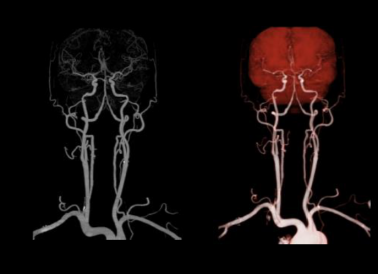

ÔÀíÏÈÈÝ:Í·¾±²¿CTA¾ßÓкÜÇ¿µÄʱ¼äºÍ¿Õ¼äµÄÇø·ÖÂÊ£¬¿É¶ÔѪ¹ÜµÄÍêÕûÐÎ̬¼°²¡±äÇéÐεÈÓèÒÔÈýÎ¬ÖØÐÞ£¬ÄÜÈ«·½Î»µØ¶ÔÂÄÚѪ¹Ü¾ÙÐÐÓÐÓõÄÊӲ죬ÇåÎúµØÏÔʾ¾±×ܶ¯Âö¡¢¾±ÄÚÍ⶯Âö¡¢×µ¶¯Âö¡¢»ùµ×¶¯Âö¼°Âµ×Wills»·µÄѪ¹ÜͼÏñ

ÁÙ´²ÓÃ;:ÂÄÚ¶¯ÂöÁö¡¢ ¶¯ÂöÖàÑùÓ²»¯¡¢ Ѫ¹Ü»ûÐΡ¢ ¶¯ÂöѪ¹ÜÏÁÕ±ÕÈû¡¢ ÂÄÚÖ×Áö